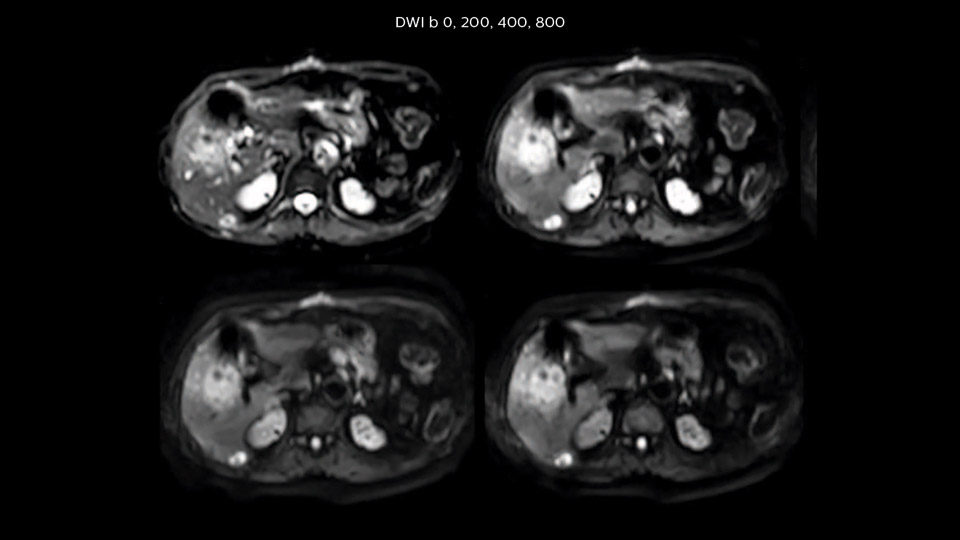

Dr. Baumann then implemented MultiVane XD for motion correction. It uses an extended reconstruction algorithm for imaging that is virtually motion free. “With MultiVane XD we get excellent motion-corrected images with high spatial resolution. We typically first optimize our scan for high image quality, and when satisfied with that, we try to reduce the scan time. So, we combined MultiVane XD with dS SENSE, which allows us to shorten the scan time,” he explains. “The performance of MultiVane XD in liver imaging is outstanding. MultiVane XD with dS SENSE is a powerful development in improving liver image quality.” “As we use breathhold imaging for T2-weighted liver scans, we depend on the patient’s ability to cooperate with the exam. This can present a real challenge when we are looking for small lesions, such as in our oncological patients. However, with MultiVane XD motion correction, we get excellent images. This is important for our surgeons, because they want to know exactly where the lesions are.”

“Our liver exams are quite fast,” says Dr. Baumann. “If the patient tolerates it, we use an arms-up position to reduce the FOV and speed up the exam with dS SENSE.” “We acquire one transversal high resolution T2-weighted sequence with 3 mm slice thickness, for example for pancreas or liver lesions. Then we also add a T2 fat suppressed MultiVane XD SPIR sequence. We perform these two routinely in our liver imaging. We use high dS SENSE factors to significantly shorten scan times to 2-4 minutes, which can improve our protocol; it’s a very robust scan.” “We include mDIXON for the dynamic sequences because of the robust and homogeneous fat suppression we get with that. We had been using eTHRIVE, but we are now quite happy with mDIXON. Sometimes we use a medication to calm the bowels, to further improve the image quality.”